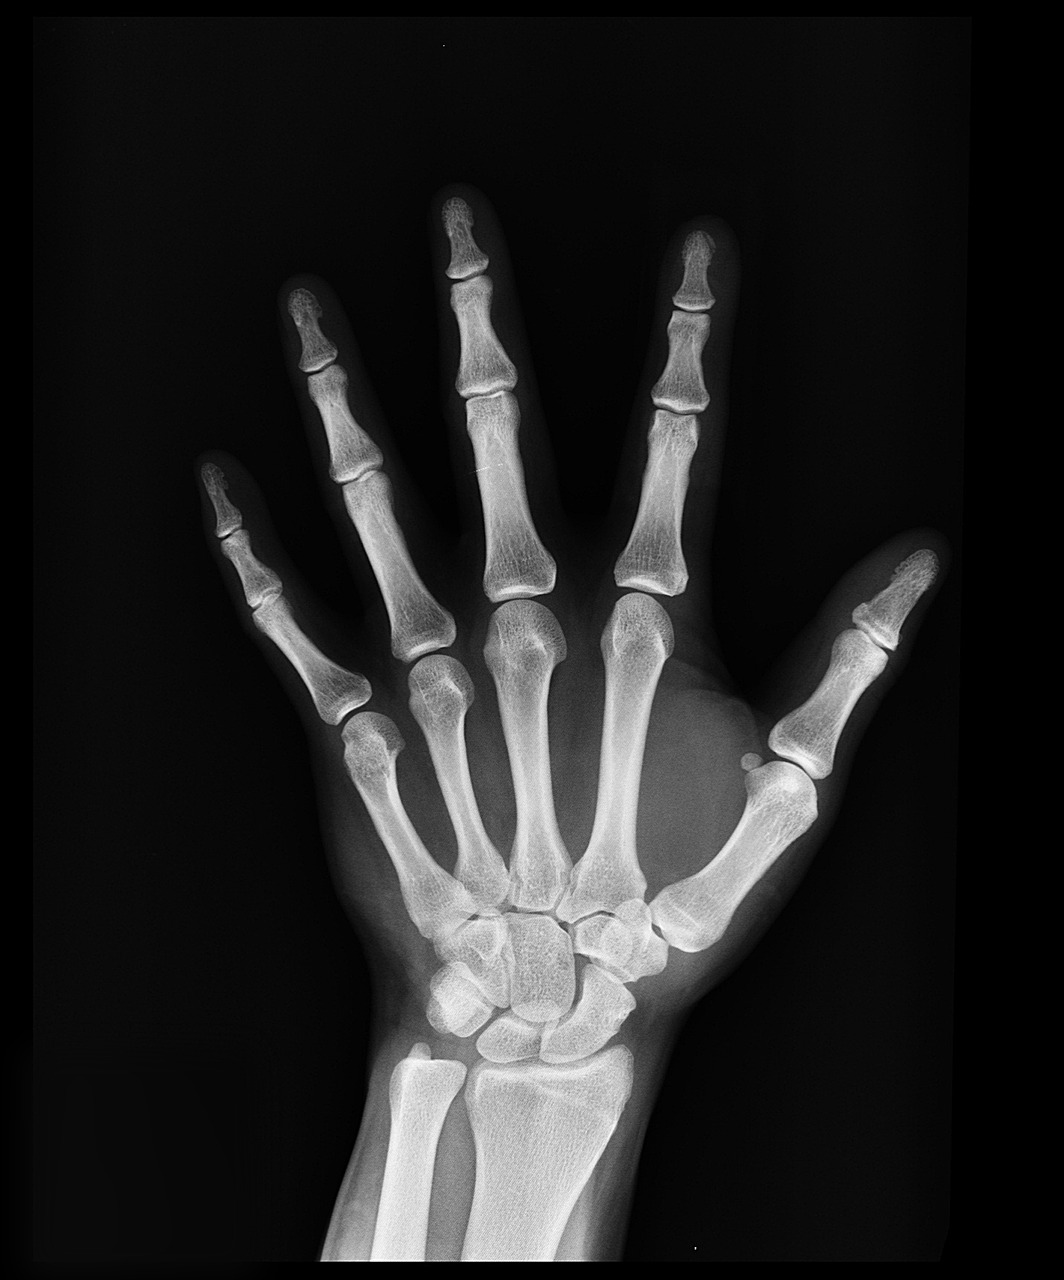

골다공증은 뼈의 밀도와 질이 감소하여 뼈가 약해지고 쉽게 골절될 수 있는 질환입니다. 특히 50대 이후, 여성은 폐경 후 에스트로겐 감소로 인해 골다공증 위험이 급격히 증가합니다. 남성도 나이가 들면서 골밀도가 감소하므로 관리가 필요합니다.